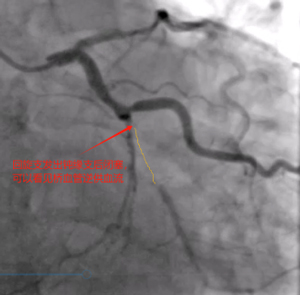

造影可见:前降支中段发出对角支后极重度狭窄,可见侧支循环右冠中远端,回旋支发出钝缘支后闭塞,可见钝缘支侧支循环回旋支远端;右冠中段闭塞。

造影结果比我预想的结果要更差,目前只有一根主血管在维持老吴的生命,情况很棘手,因为近期有过消化道出血情况,术中紧急会诊后,及时与家属沟通,综合评定后再行下一步治疗。手术下台时我给老吴简单的说了一下目前情况,老吴也同意了。